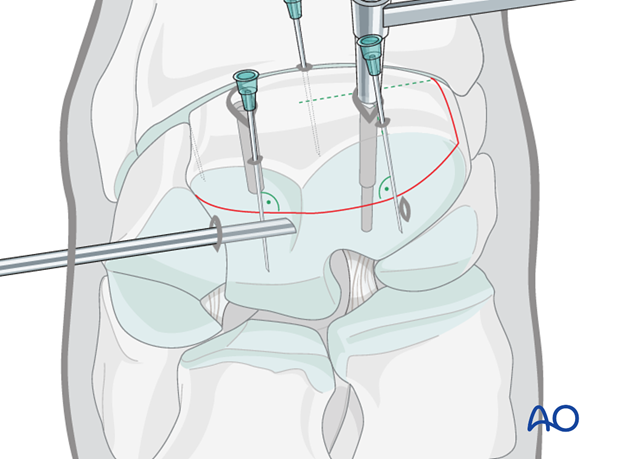

The proximal medial and lateral margins of the fracture are defined by arthroscopically guided percutaneous insertion of 18 gauge hypodermic needles.

It is important that these needles are placed perpendicular to the dorsal surface of the carpus in order to accurately delineate the fracture width.

Two 18 gauge spinal needles are then placed over the central portion of the radial and intermediate facets of the third carpal bone. These two needles are close and parallel to the proximal articular surface and directed approximately perpendicular to the fracture line. These needles are critical guides for implant placement. Once the spinal needles have been placed, the lateral and medial hypodermic needles are removed.

A further 18 gauge needle is inserted into the carpometacarpal joint.